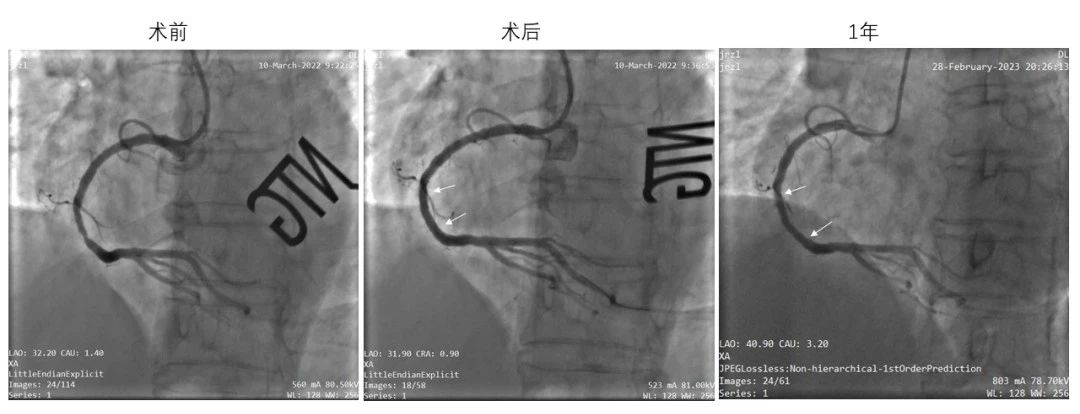

(左:术前靶病变处造影;中:IBS®支架植入后造影;右:术后1年造影,结果显示支架内通畅,未见明显狭窄)

IBS®冠脉支架的可行性临床研究(FIM,即I期临床研究)于2018年开始受试者入组,目前已顺利完成4年随访,结果表明其在简单原发性冠脉病变中具有良好的中期安全有效性。血管造影(QCA)及血管内光学相干成像(OCT)测量显示,IBS®冠脉支架植入6个月后靶病变平均管腔面积略有增大的趋势,说明IBS®冠脉支架逐渐降解后可能会对血管带来正向重塑,从而有望真正体现“介入无植入”的理念和优势。